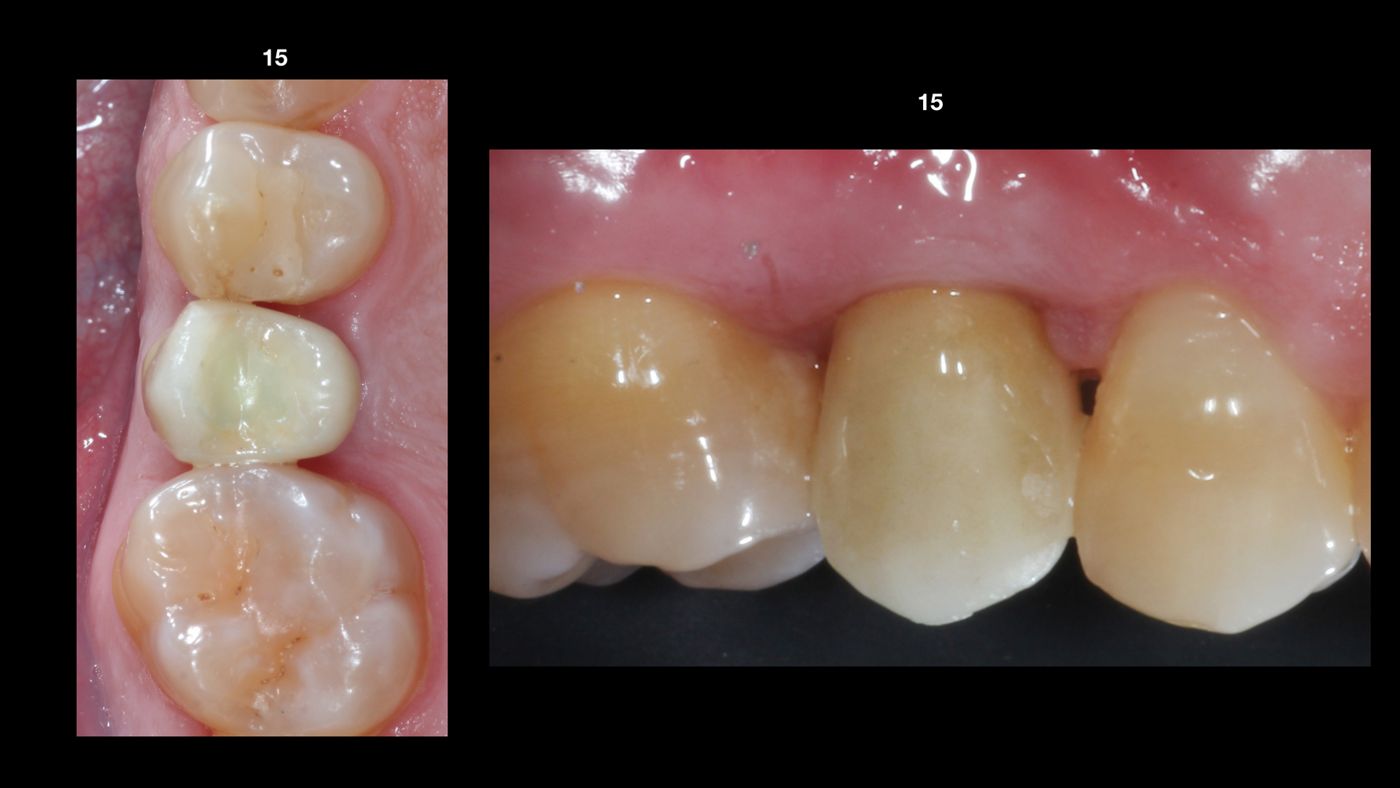

A 45-year-old male patient came to our clinic to restore the two fractured upper second premolars (15 and 25) (Fig. 1). His personal history was unremarkable; he was a non-smoker with no systemic diseases (ASA I) or periodontal disease. After clinical and radiological analyses, an immediate implant placement and loading protocol was decided.

Due to the systemic and local healthy situation, the immediate protocol was planned. Clinical examination of both premolars revealed no gingival recession, adequate width and thickness of keratinized gingiva (thick biotype) (Fig. 1), a shallow probing pocket depth and no bleeding on probing. From a radiological diagnosis we confirmed an integral and thick buccal bone plate, no radiolucency at the apex, good bone availability and alignment between the roots and the alveolar crest (Figs. 2-3). After the prosthetic analyses (casts, wax-up and smile design), we proceeded to design and manufacture two provisional crowns and create a surgical stent. With all this information we planned to use two 3.75 mm x 12 mm Straumann® BLX, Roxolid®, SLActive® implants with two 2.5 mm SRAs height.

The result was successful in terms of health, esthetics and function (Fig. 15). At the 3- and 6-month follow-ups we noted the maintenance of the peri-implant interproximal bone level and the good gingival contouring on both sides (Figs. 16-17).